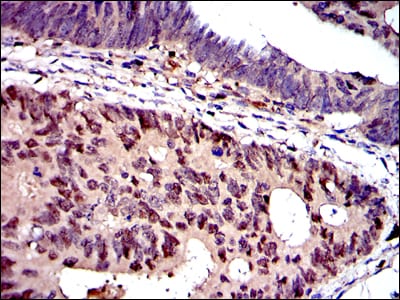

![MCM2 Mouse mAb[63919]](https://img1.dxycdn.com/p/s14/2025/0922/534/2933805038726699691.jpg)

Immunohistochemical analysis of paraffin-embedded human colon cancer tissues using MCM2 mouse mAb with DAB staining.